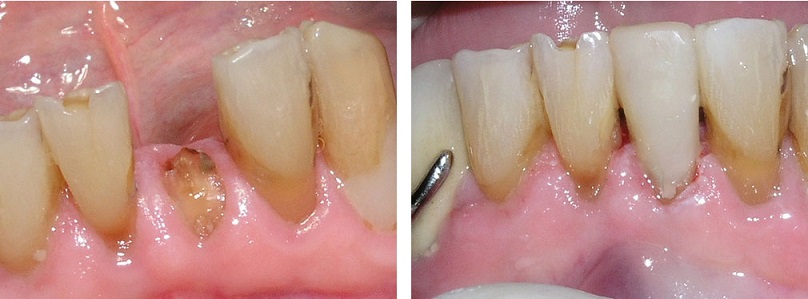

The first step in placing a post is performing root canal therapy on the tooth to remove the infection and shape the root canal to receive the post. We'll use a small instrument called a dental file to shape the top of the root canal, select a post, and then cement or bond it in place. After the post is in place, we fill the tooth with the new core material. Once it has hardened, the core material is shaped and prepared to receive a crown. We then take an impression of your teeth so a dental laboratory can custom-craft a crown that will precisely fit your tooth.

A tooth needing a root canal usually has a large filling or lots of decay and most of the original tooth is gone. During a root canal, a hole is drilled though the natural crown. The hole goes all the way through the center of the crown into the roots and the root canal is done through this hole. The drilled out area inside the tooth is called the core of the crown. All teeth need a dental crown after a root canal. For the crown to be successful, it must have a good foundation. The core build-up provides this support. It also replaces the original shape of the tooth so that it will be easier to design a crown.

After a root canal is done, all of the old filling and decay are removed. This leaves a shell of a tooth and a core build up replaces the missing tooth material. The remaining tooth is cleaned and special composite filling material or dental amalgam is placed into the core. The material replaces the entire missing tooth and strengthens what's left to prevent breakage.